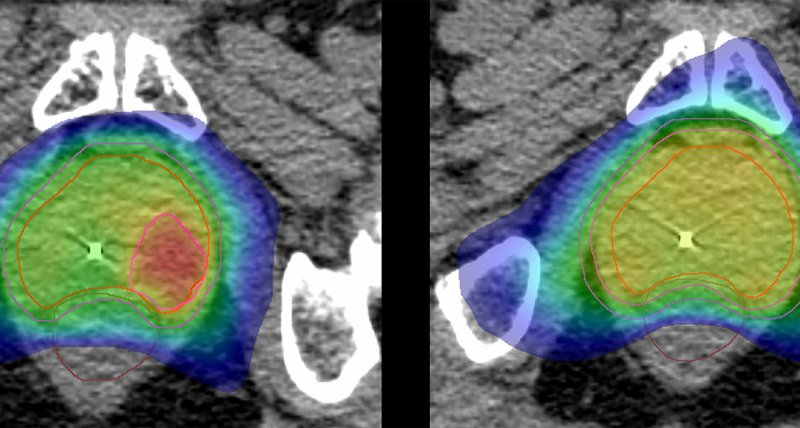

Freiburg – Prostatakrebs ist die häufigste Krebserkrankung bei Männern in Europa. Eine Arbeitsgruppe des Universitätsklinikums Freiburg arbeitet daran, jene Bereiche des Organs, in denen eine hochpräzise Bildgebung den Tumor anzeigt, mit besonderer Intensität zu bestrahlen.

Dies soll die Therapie effektiver machen und das umliegende Gewebe schonen, zum Beispiel Blase und Darm. Zudem könnte sich die Behandlungszeit deutlich verkürzen. Das Bundesministerium für Bildung und Forschung (BMBF) fördert das Vorhaben namens „HypoFocal-SBRT“ mit rund 2,8 Millionen Euro über vier Jahre mit der Option auf Verlängerung um weitere vier Jahre.